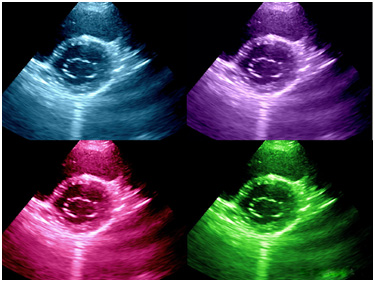

Colourful Image Of Modern Ultrasound Monitor Stock Photo - Image Of

www.dreamstime.comultrasound

www.dreamstime.comultrasound